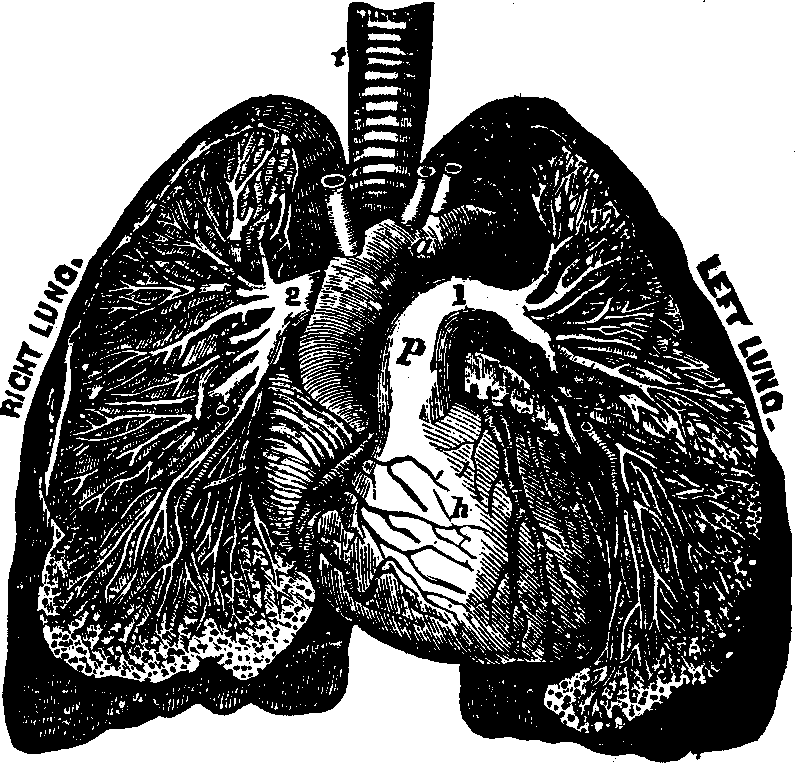

roots of the eyelashes. The oily nature of this secretion prevents the

tears, when not stimulated by emotion, from overflowing the lachrymal

canal.

Mucus. The mucous membranes are provided with minute glands which

secrete a viscid, gelatinous matter, called mucus. The peculiar

animal matter which it contains is termed mucosin. These glands are

most numerous in the Pharynx, Esophagus, Trachea, Bronchia, Vagina and